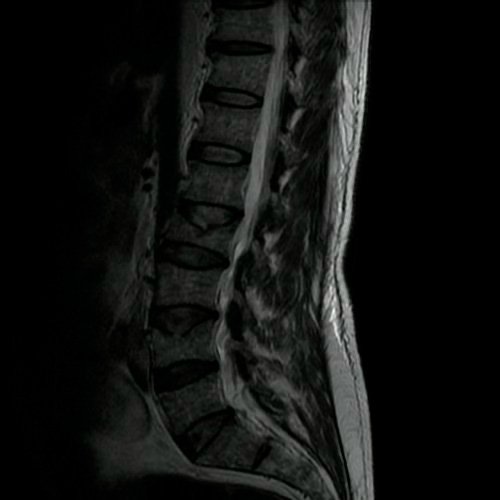

- Resonancia magnética de columna lumbar (28/08/2025): fractura aplastamiento de L2, a expensas de su platillo superior, que compromete el 60% de su altura. Fractura aplastamiento de L4 y L5, a expensas de platillos superiores, que afecta menos del 30% de la altura del cuerpo vertebral, sin desplazamiento. Estos cuerpos vertebrales presentan impronta de Schmorl en la placa terminal superior y resultan hiperintensos en STIR, hipointenso en T1, hallazgo compatible con edema óseo.

- Tomografía de columna lumbosacra (Día 0): Contamos con TC previa del día 04-09-2025 y RMI del día 28-08-2025. Hiperlordosis lumbar. Eje lumbar se encuentra desviado hacia la derecha. Persiste, de mayor jerarquía que en TC previa, la reducción de altura de los cuerpos vertebrales de D12, L2, mayor al 50%, con afectación del muro posterior. También se observa reducción del 30 % del cuerpo vertebral L4 y L5. Hallazgos en relación a fracturas aplastamiento patológicas. Además se observa marcada osteopenia generalizada. Disminución de la altura intervertebral de L2-L3 y L3-L4, a nivel de su margen posterior. Los demás espacios discales visualizados son de altura conservada. No se observan signos de protrusiones ni hernias discales. Ligera rarefacción del TCS paravertebral.